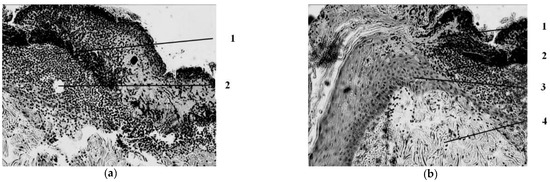

Seven days after the injury, the animals in the wounds of the control group (treatment with Levomecol) showed a picture of inflammation with initial signs of healing (Figure 2).

The wound is covered with a scab, which consists of necrotized tissues (epidermis, dermis), and in the center of the wound, where the burn was deepest, its own muscle is included in its skin. On the periphery, closer to the edges of the wound, approximately in the middle of the thickness of the dermis, a pronounced leukocyte demarcation shaft is found, which divides the dermis into three parts—upper, necrotized, and lower—with manifestations of regeneration in the form of proliferation of epithelial cells in the course of pre-existing hair follicles and initial manifestations of marginal epithelialization of the wound, foci of fibroblast proliferation in the dermis with the appearance of newly formed collagen fibers and thin-walled blood vessels, and in muscle tissue against the background of dystrophically altered, and even necrotized muscle fibers with the phenomena of sarcoplasm decay are sometimes found as manifestations of regeneration in the form of muscle kidneys. Proliferation of myocyte nuclei is noted along the periphery of a significant part of viable muscle fibers. In addition, fibroblasts proliferate between muscle fibers. In the loose connective tissue under the skin’s own muscle, there is a proliferation of connective tissue cells in these areas.

Figure 2. Morphological changes in the wound seven days after the application of the burn and subsequent treatment with Levomecol ointment. Initial manifestations of marginal epithelialization. 1—scab; 2—regenerating epidermis with signs of regeneration (beginning of marginal epithelization). Staining with hematoxylin and eosin. magn. ×50.